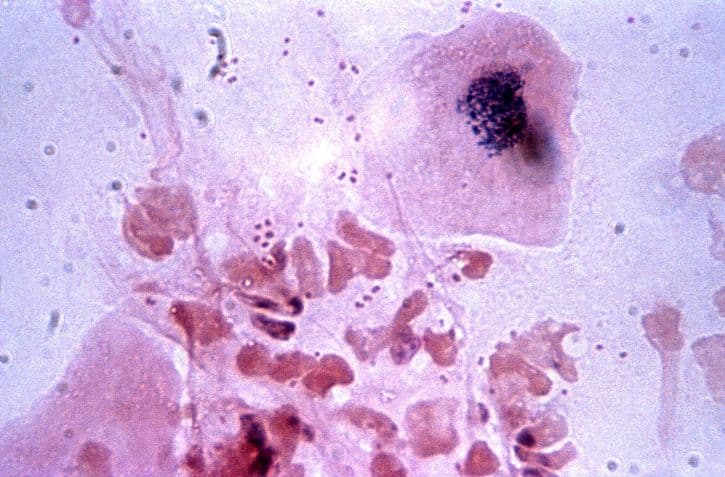

아직 걱정할 수준은 아니고 정상범위에서 아주 조금 벗어난 수준이라고 하셔서 안심이 되었지만 집에 와서 백혈구 수치 낮으면 어떠한 증상이 있고 어떻게 관리를 해야하는지 알아보게 되었던 것으로 보입니다. 저처럼 이러한 결과를 받아보신 분들이 저 말고도 많이 있으실테니 오늘은 백혈구 수치에 대해서 함께 알아보는 시간을 가지려 하는 것으로 전해지고 있습니다. 일단 그 전에는 저는 백혈구라는 것이 정확히 무엇인지에 대해서부터 알아보게 되었는데요. 한편 백혈구는 전체 혈구에서 약 1퍼센트 이하의 비율로 차지를 하고 있으며 건강상태를 유지하며 바이러스와 세균과 같이 외부물질로 인해 발생할 수 있는 질환들을 예방하며 면역 기능을 수행하는 세포라고 알려져 있습니다. 이러한 백혈구는 총 5개의 종류로 나뉘어지게 되는 것으로 전해지고 있는데 림프구, 호중구, 호산구, 단구, 호

염기구로 나뉘어지며 백혈구의 정상적인 수치는 성인을 기준으로 하여 5000~10000정도라고 보시면 되는 것으로 알려져 있습니다. 이러한 수치보다 낮게 측정이 되게 되면 5종류 중에서 하나의 백혈구가 비정상적으로 낮아지게 되는 것이라 볼 수 있는 것으로 전해지고 있습니다. 백혈구 수가 감소하게 되면 면역기능이 낮아지게 되고 감염 위험이 증가하게 되면서 생명을 위협하는 상황이 오게 될 수도 있게 되는 것으로 알려져 있는데요. 또한 이렇게 백혈구 수치 낮으면 그에 대한 원인을 많이 찾아볼 수 있는데 인체면역결핍바이러스병이나 골수질환, 비장 질환이나 간 질환, 호중구감소증, 자가면역질환과 같은 질병으로부터 그 원인을 찾을 수 있기도 하는 것으로 전해지고 있습니다. 인체면역결핍바이러스가 그 원인이라고 하면 에이즈에 걸리게 될수도 있는 것으로 보이는데 세균과 곰팡이등